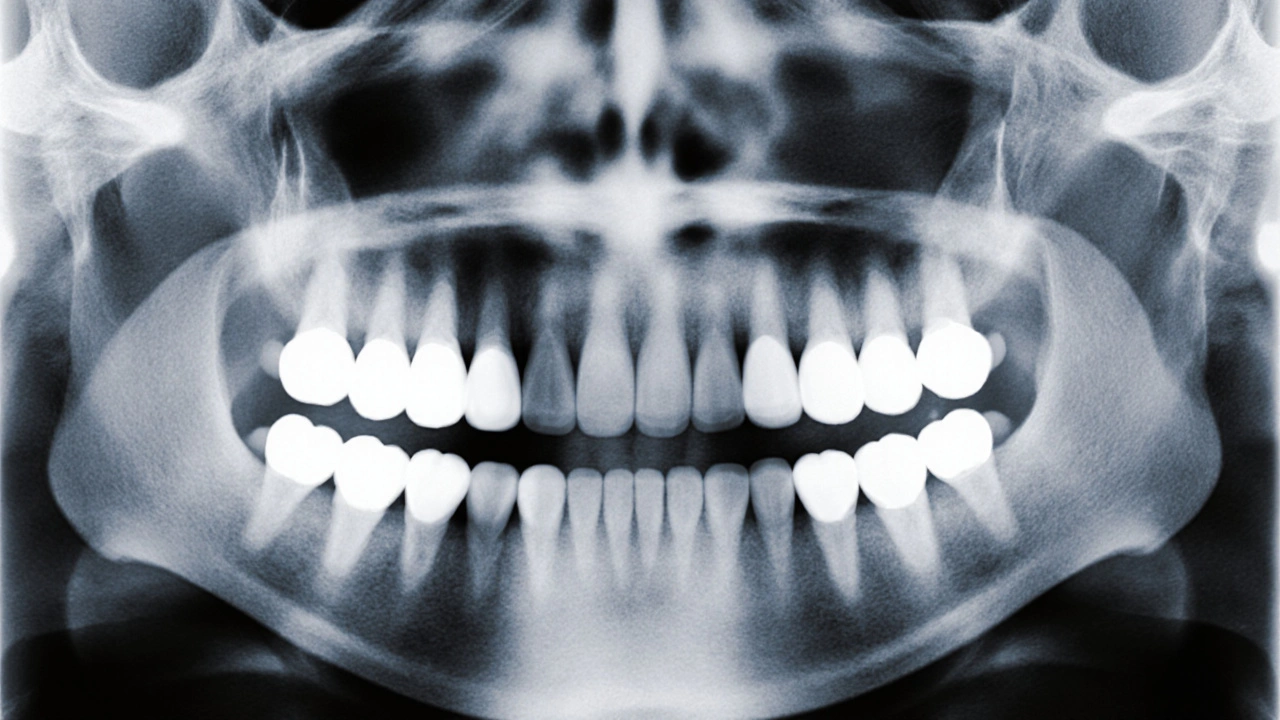

Profesionální diagnóza zahrnuje klinické vyšetření a často také rentgen (panoramatický snímek čelistí). Rentgenové snímky ukazují, jak hluboko je zub pod dásní, jestli má správný úhel růstu a jestli není blokován jinými zuby.